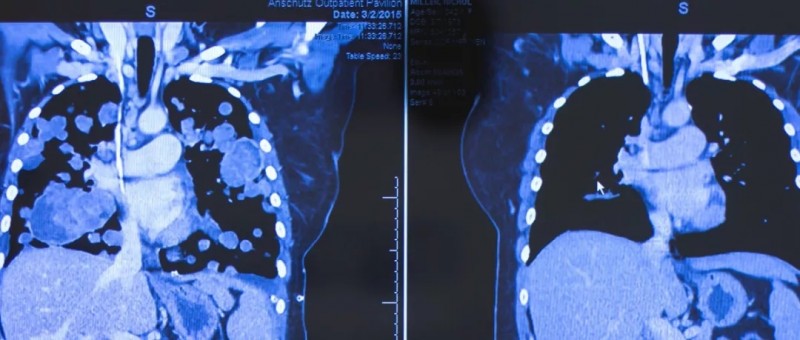

喜悦的泪水从Nichol Miller的眼中涌出。她不可置信的看着自己的CT扫描结果,是清晰和健康的肺部结构,当初双肺大大小小,密密麻麻的肿瘤如今已消失殆尽。

Nichol Miller不敢相信的看着自己的CT结果,马上把这个好消息告诉丈夫,并给了自己的医生一个感激的拥抱

就在四个月前,肿瘤已经填满了她双肺的90%,她连呼吸都困难,需要一直吸氧才能维持,她的生命即将走到尽头。而美国一种新型的抗癌药物完全改变了她的生死!